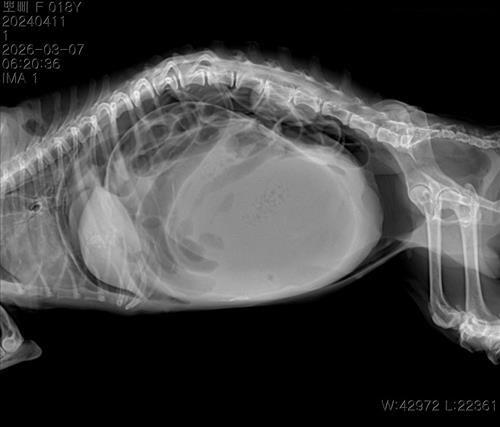

17살 말티즈 1.6 kg 였습니다. 엑스레이 하나는 복부팽창 찍은 이떄 혼수상태 일겁니다 또 다른 하나 사진은 이미 혼수상태 쇼크상태에서 천자 한 후 찍은 엑스레이 사진입니다

3월 7일 새벽에 갑작스러운 복부 팽창이 심하게 생겼습니다.

의사 말로는 복부 팽창 원인은 장기 파손, 종양으로 보이는 큰 덩어리였습니다

종양 파열 같다는 말 같습니다 제 생각엔 의사말이 맞는지도 궁금합니다

의사말 1번쨰 엑스레이 찍었을때 장기파열 두번쨰 뽀삐가 쇼크가 오고 혼수상태 일때 천자후 두번쨰 엑스레이 찍을때는 큰 덩어리로 보이는 종양 이라고 하였습니다